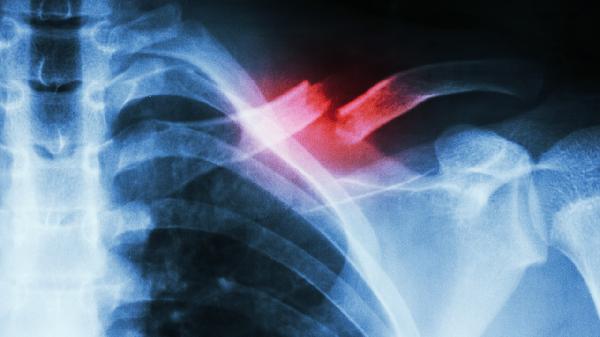

病理性骨折通常发生在原有骨骼病变基础上,如骨质疏松、骨肿瘤或骨髓炎等疾病导致骨质强度下降,轻微外力甚至日常活动即可诱发骨折。这类骨折常见于脊柱、股骨颈等承重部位,X线检查可见骨折线周围存在溶骨性破坏或成骨性病变。患者可能伴有原发病症状如夜间骨痛、体重下降,治疗需兼顾骨折固定与原发病控制,例如使用唑来膦酸注射液抑制骨吸收,或针对肿瘤进行放化疗。